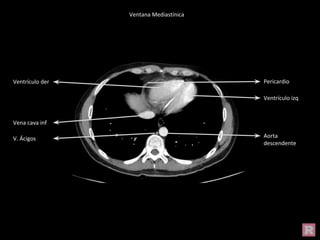

Ventana Mediastínica

Ventana Pulmonar

Cúpula

diafragmática

Ventrículo izq

Ventrículo der

Esófago

V. Ácigos

Vena cava inf

Aorta

descendente

Pericardio